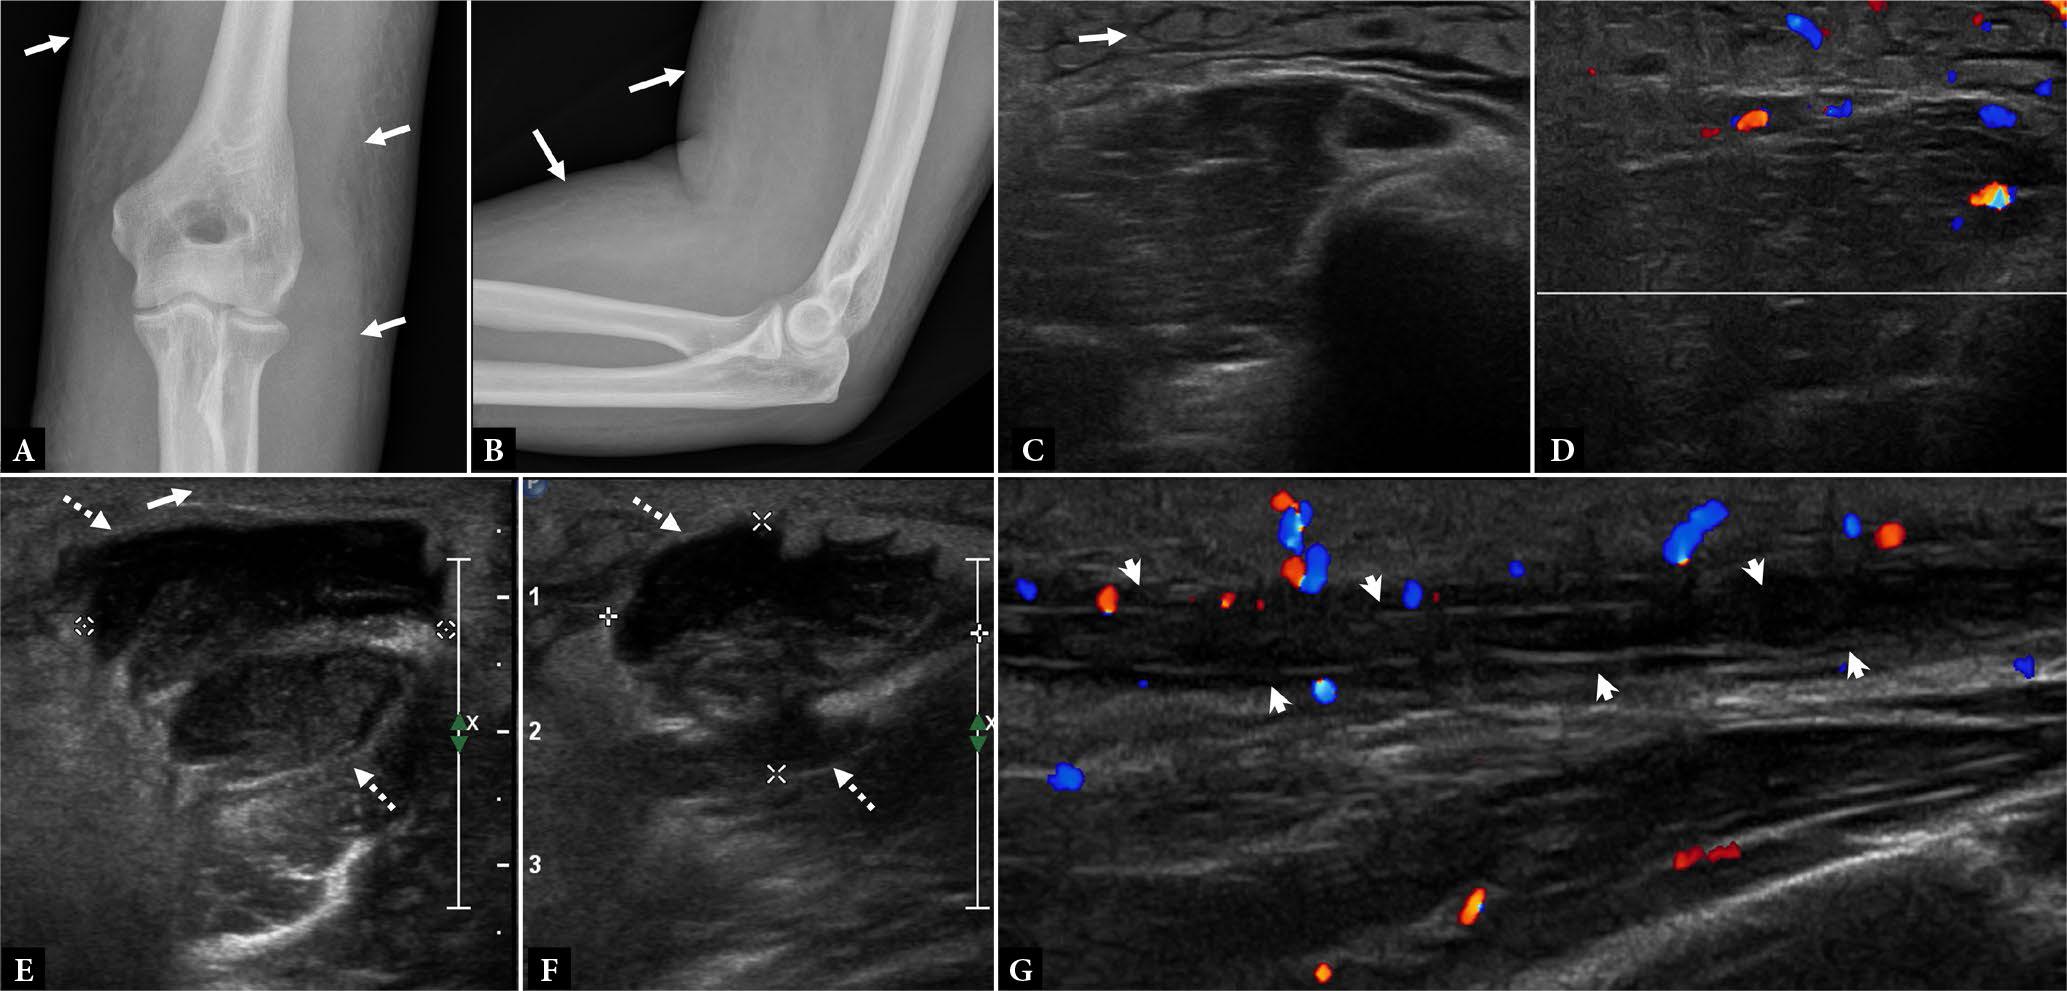

Fig. 2.